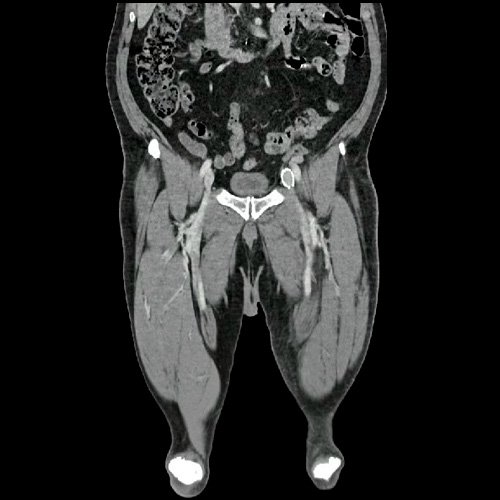

• Flebotomografia de miembros inferiores (Día 18): Filtro de vena cava inferior infrayacente a venas renales. Stent metálico a nivel de la vena ilíaca común y externa izquierda, permeable. Se explora la región venosa del territorio femoral y poplíteo, evidenciándose defectos parciales de relleno endoluminal a nivel de la vena femoral superficial y profunda izquierdas, compatibles con trombosis venosa parcial. A nivel del tercio distal de la vena femoral común izquierda, se evidencia aumento de calibre e interrupción brusca de la opacificación del contraste (“signo de stop”), compatible con trombosis venosa oclusiva en dicho nivel, sin opacificación venosa distal. Se observan similares hallazgos a nivel de la vena femoral superficial contralateral, evidenciándose defectos de relleno endoluminal parcial hasta su tercio distal, con ausencia de opacificación distal. Salvo mejor criterio sugiero complementar con eco-Doppler de venoso de ambos miembros inferiores. Presenta edema difuso de los tejidos blandos de miembro inferior izquierdo. Se observa en los tejidos blandos de la región inguinal izquierda, colección hipodensa con realce periférico que mide 4.7 cm AP x 4 cm. Además se observan ganglios locorregionales aumentados en número y tamaño, algunos de rango megálico.

Flebotomografia de miembros inferiores (Día 18)